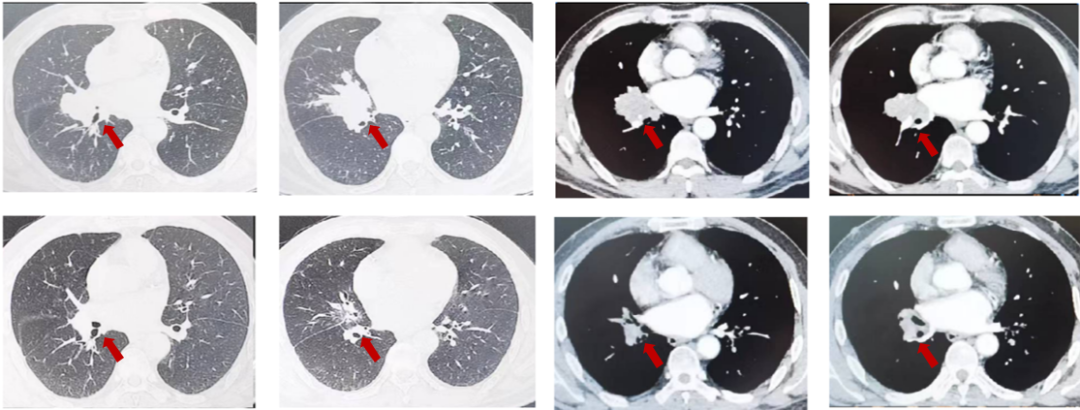

患者王XX,男,54岁,2023年4月以“咳嗽1个月”入院,PS1分,高血压3年,行替米沙坦40毫克日1次口服血压控制好,否认冠心病,糖尿病等病史,吸烟史:吸烟30年,每天20支。肺CT(外院,2023-3):右肺中叶肿物,32mm*37mm,边缘见分叶,纵隔淋巴结肿大,右肺中叶中心型肺癌?邻近上叶前段局部受累不除外。右肺中叶炎症。双肺气肿、肺大泡。肝脏多发小囊肿。支气管镜:右肺中叶见新生物,表面有坏死物附着,堵塞管腔,取病理。病理:鳞癌。PD-L1(DAKO 22C3)(+,CPS=20)。cT2bN2M0,ⅢA期。经MDT讨论后,患者为可切除手术患者,建议新辅助治疗。给予患者3周期特瑞普利单抗+紫杉醇/卡铂治疗,3周期评效PR。

图3:由上至下分别展示基线(A.)及免疫化学治疗后改变(B.)。红色箭头指示病灶位置,由左至右分别为右肺肿物肺窗、右肺肿物纵隔窗。

患者2023年7月,于我院行单孔胸腔镜下右肺中下叶切除,肺门纵隔淋巴结清扫、胸膜粘连松解术。术后病理:(右肺中下叶)治疗后标本,未见癌细胞,符合治疗后改变,请密切结合原病理报告。(淋巴结)未见转移癌0/17,2组0/5,4组0/2,7组0/2,8组0/1,9组0/2,10组0/2,11组0/2,12组0/1。pT0N0M0,达PCR,术后行1周期特瑞普利单抗+紫杉醇/卡铂治疗,13周期特瑞普利单抗维持治疗,DFS23个月,目前随访中。